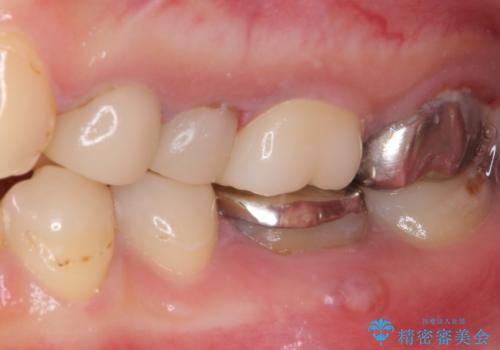

結婚式前に目立つ銀歯をセラミックに

- 笑ったときに見てしまう上顎奥歯の銀歯を気にして来院された患者様です。

折角セラミッククラウンを装着するので、根管治療を行った後に補綴治療を行うこととしました。

他にも目立つ銀歯がありましたが、最も気にしている2本を優先して行うこととしました。

結婚式前にはクリーニングやホワイトニングを行い、その後他の歯を治療していく予定です。